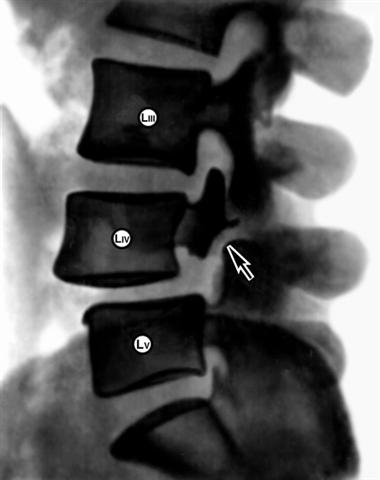

Рис. 3. Рентгенограмма нижней части поясничного отдела позвоночника (боковая проекция) при спондилолистезе IV поясничного позвонка на фоне спондилолиза: тело IV поясничного позвонка смещено вперед по отношению к нижележащему позвонку, стрелкой указана расщелина в межсуставном участке дуги позвонка (спондилолиз). |